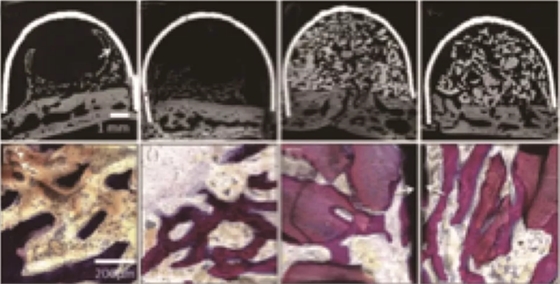

因?yàn)镻RF中含有生長因子,而體外實(shí)驗(yàn)也證明了這些生長因子具有一定的促進(jìn)成骨效果。學(xué)者也將其應(yīng)用到了促進(jìn)成骨的動物實(shí)驗(yàn)中,Knapen等在兔的顱骨中研究了PRF的促進(jìn)成骨效果[5],結(jié)果在組織學(xué)和組織形態(tài)定量學(xué)的分析中(圖2、3)都沒能發(fā)現(xiàn)PRF有任何附加的影響。

Nejat在上頜竇外提升術(shù)中研究了PRF促進(jìn)成骨的效果[6],在實(shí)驗(yàn)中對照單獨(dú)使用Bio-oss和Bio-oss聯(lián)合PRF在上頜竇提升術(shù)中的應(yīng)用,在6個月的愈合期之后,對新生骨進(jìn)行組織學(xué)和組織形態(tài)定量分析(圖4),發(fā)現(xiàn)兩組沒有差異。這就說明了PRF的使用并不能帶來更多更好的成骨效果。